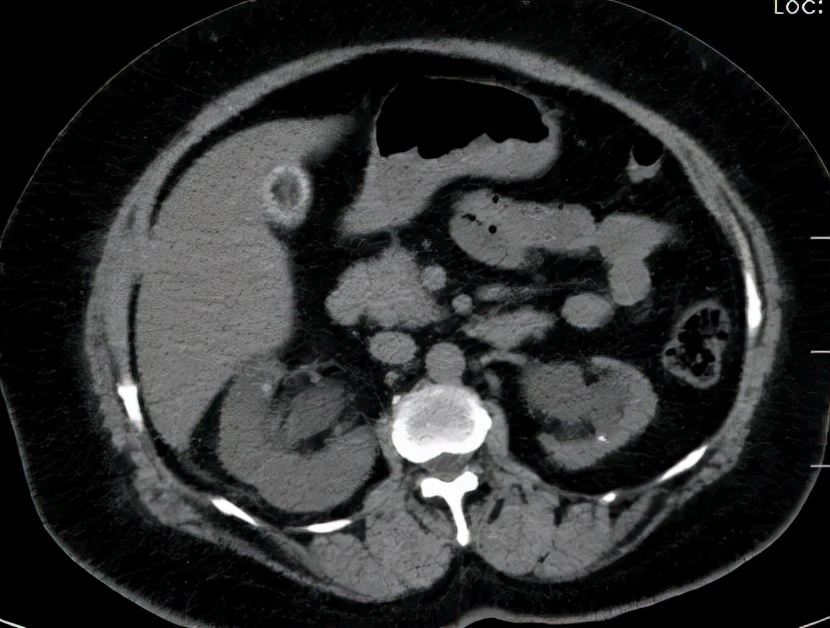

王卫国看了她的肾CT片子后解释说

你的左肾有结石、左输尿管也有结石

左肾明显萎缩表现,但仍有保留价值

查血发现血象很高,肾功能也不行了

原来是王大妈的右肾结石掉了出来

形成右输尿管结石合并肾积脓,尿源性脓毒症

再加上王大妈左肾有结石且明显萎缩

双肾梗阻,同时发生了急性肾功能不全